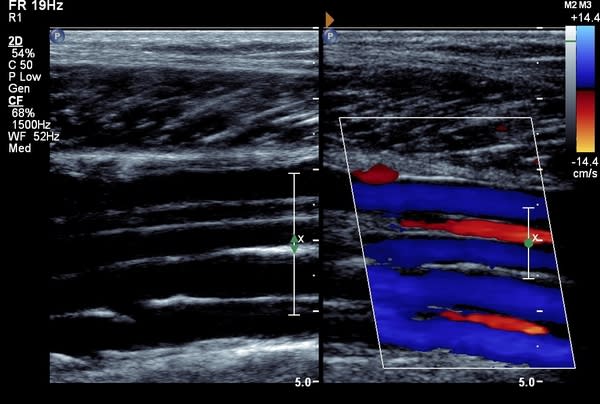

Deep vein thrombosis (DVT) is a serious condition where a blood clot develops, often in the deep veins of the legs but occasionally in the pelvis. It can be fatal if the clot dislodges and travels to the lungs.

Numi Scan offer a same day service to diagnose leg DVT for £120